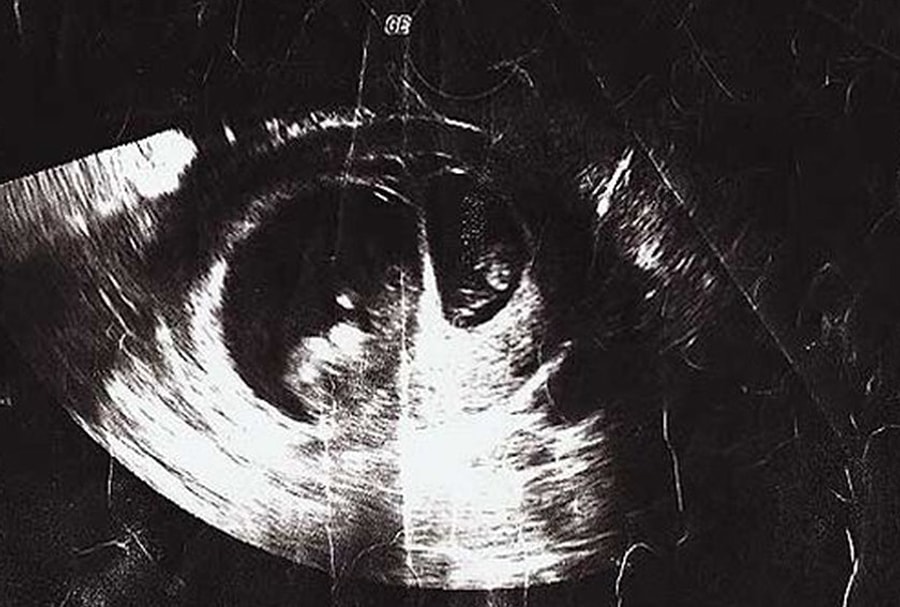

лодный мешок узи

Плодный мешок узи 87 фото